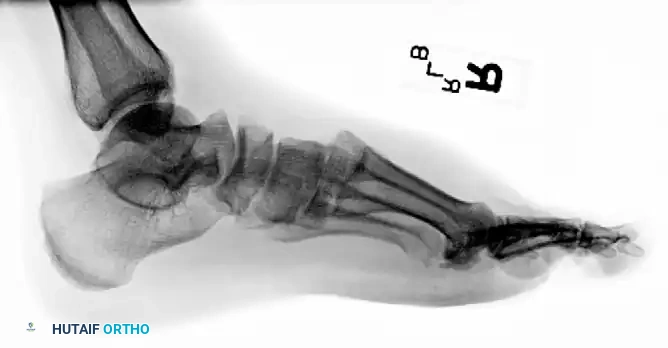

The midfoot serves as the critical biomechanical transition zone between the rigid hindfoot and the flexible forefoot. Injuries to this region, particularly tarsometatarsal (Lisfranc) fracture-dislocations and proximal fifth metatarsal fractures, present significant challenges to the orthopaedic surgeon. Missed diagnoses or inadequate reductions inevitably lead to post-traumatic arthrosis, midfoot collapse, and profound functional disability.

The stability of the tarsometatarsal (TMT) joint complex relies on both its intrinsic bony architecture and a robust ligamentous network. The base of the second metatarsal is recessed proximally between the medial and lateral cuneiforms, creating a "keystone" configuration that locks the midfoot.

Crucially, there is no transverse ligament connecting the bases of the first and second metatarsals. The primary stabilizing structure is the Lisfranc ligament, a thick, oblique interosseous band originating from the lateral aspect of the medial cuneiform and inserting onto the medial base of the second metatarsal. Disruption of this ligament, either through direct crush injuries or indirect axial loading on a plantarflexed foot, leads to catastrophic destabilization of the medial column.